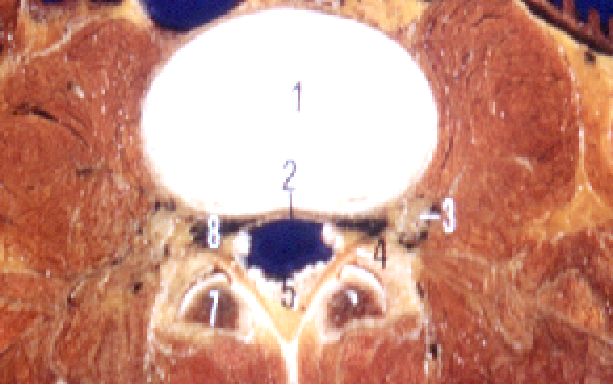

一、椎管的应用解剖

-

前壁:椎体、纤维环、后纵韧带。

后壁:椎弓和黄韧带。

两侧:椎弓根、上下关节突及关节囊,并以椎间孔向外开放。

黄韧带:起于上位椎管的下前缘,止于下位椎管的上后缘。

中央椎管:各腰椎椎孔形状,腰1、2多呈卵圆形,腰3、4多呈三角形,腰5多呈三叶形,其他尚可呈钟形、或橄榄形。因退变或其他病变、椎孔形状还可有不同改变。腰椎椎管自腰1、2间隙以下包含马尾神根.其被硬脊膜包围的部分形成硬膜囊,各种经根自硬膜囊发出后在椎管内的一段称为神经根管,以后分别自相应椎间孔穿出。

腰神经通道:腰神经根自硬脊膜囊发出后,经过较窄的骨纤维性管道,由椎间管穿出的径路统称为腰神经通道。此通道分为两段,第一段为神经根管,从硬膜囊穿出点至椎间管内口,第2段为椎间管

盘黄间隙:即椎间盘与黄韧带之间的间隙。

侧隐窝:侧隐窝位于侧椎管,也是神经根管的狭窄部分。